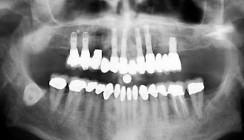

Die 51-jährige Patientin stellte sich mit einem insuffizienten Zahnersatz und erheblicher, weit fortgeschrittener Atrophie vor. Bei der röntgenologischen Analyse war erkennbar, dass – wie oben ausgeführt – die Resorption der gesamten Maxilla, sowohl im anterioren als auch im posterioren Bereich, eine Implantation zunächst unmöglich erscheinen ließ (Abb. 1). Nach Beratung und Aufklärung wollte die Patientin dennoch einen festsitzenden, wenn möglich keramikverblendeten Brückenzahnersatz.

Die Allgemeinanamnese der nicht rauchenden Patientin war unauffällig. Die Restzähne des Oberkiefers, zwei Molaren im ersten und ein Molar im zweiten Quadranten, waren aus parodontalen Gründen nicht erhaltungswürdig und mussten nach der Rehabilitation entfernt werden. Nach Angaben der Patientin mussten die Zähne des Ober- und Unterkiefers in den letzten Jahren sukzessiv, wegen ständigen Infektionen und anhaltenden Schmerzen, extrahiert werden.

Im Unterkiefer war, als Antagonist für die vorgesehene Oberkieferrestauration, ein rein implantatgetragener kunststoffverblendeter Brückenzahnersatz, bereits seit vielen Jahren mit guter Prognose, in situ (Abb. 2a und b).